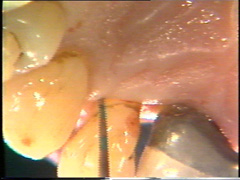

Periodontología Diagnóstico Limpieza subgingival Incisiones Remoción del tejido de garnulación Reubicación de los colgajos Sutura Chequeo postoperatorio mediato |

Limpieza subgingival de las raíces. |

El tratamiento inicial consiste en el raspado y alisado radicular subgingival bajo anestesia local. Como resultado de este tratamiento el margen gingival se ha retraído. Sin embargo en la región de la furcación las señales de patología permanecían y las profundidades de bolsa al sondaje todavía eran 6 mm o más en cada una de las raíces. |